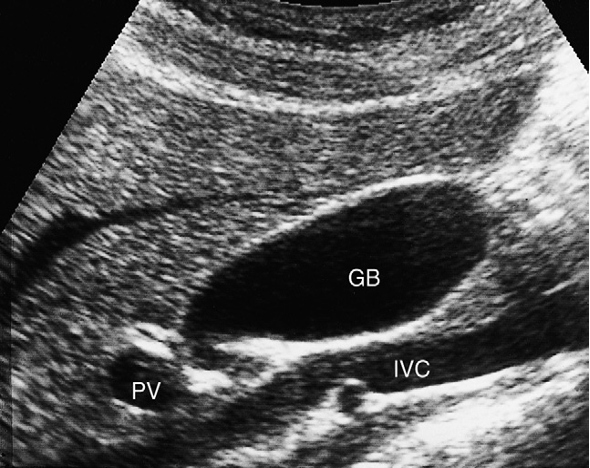

The normal hepatic parenchyma is of uniform echogenicity, composed of medium and low level echoes, interspersed with the bright echoes of the portal triads and echo-free areas corresponding to large hepatic veins.

1st Ultrasound of normal liver showing a uniform echo pattern interspersed with bright echoes of portal triads and echo-free areas of hepatic and portal veins